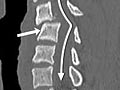

Computed Tomography (CT) Scan of the Spine

Computed Tomography (CT) Scan of the SpineSkip to the navigationTest OverviewA CT scan uses

X-rays to make detailed pictures of the spine and vertebrae. During the

ResultsA computed tomography (CT) scan uses

X-rays to make detailed pictures of the

spine and vertebrae in the neck (cervical spine),

upper back (thoracic spine), or lower back (lumbosacral spine). Complete

results usually are ready for your doctor in 1 to 2 days. CT scan of the spine Normal: | Spinal bones (vertebrae) are

normal in shape, number, and alignment. |